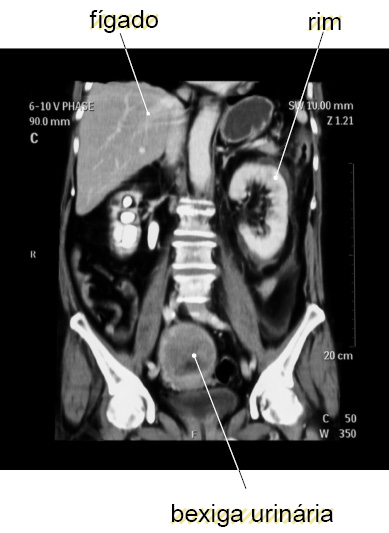

1. Nível de órgão. Um órgão é composto de dois ou mais tipos de tecido que realizam uma ou mais funções comuns. A bexiga urinária, o coração, o estômago e o pulmão são exemplos de órgãos.

1. Nível de sistema de órgãos. Um sistema de órgãos é um grupo de órgãos que juntos realizam uma função comum ou um conjunto de funções e são, portanto, vistos como uma unidade. Por exemplo, o sistema urinário consiste nos rins, ureteres, bexiga urinária e uretra. Os rins produzem urina, que é transportada pelos ureteres à bexiga urinária, onde ela é estocada e eliminada do corpo através da uretra. [...]